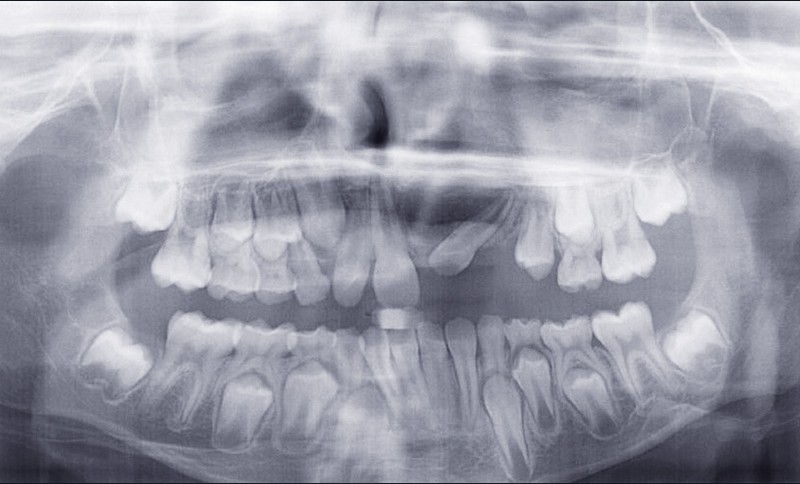

Le jeune Yoan 9 ans est adressé par son chirurgien maxillofacial, suite à l’exérèse d’un kyste bénin du maxillaire, et l’avulsion de 21 et 23 (fig. 1). L’apex de 22 a été soufflé par le kyste. La céphalométrie (fig. 2a et b) et l’examen clinique mettent en évidence une classe II squelettique par rétromandibulie, ainsi qu’une classe II dentaire. Le patient, est particulièrement perturbé par l’intervention qu’il vient de subir, et la coopération s’annonce difficile.